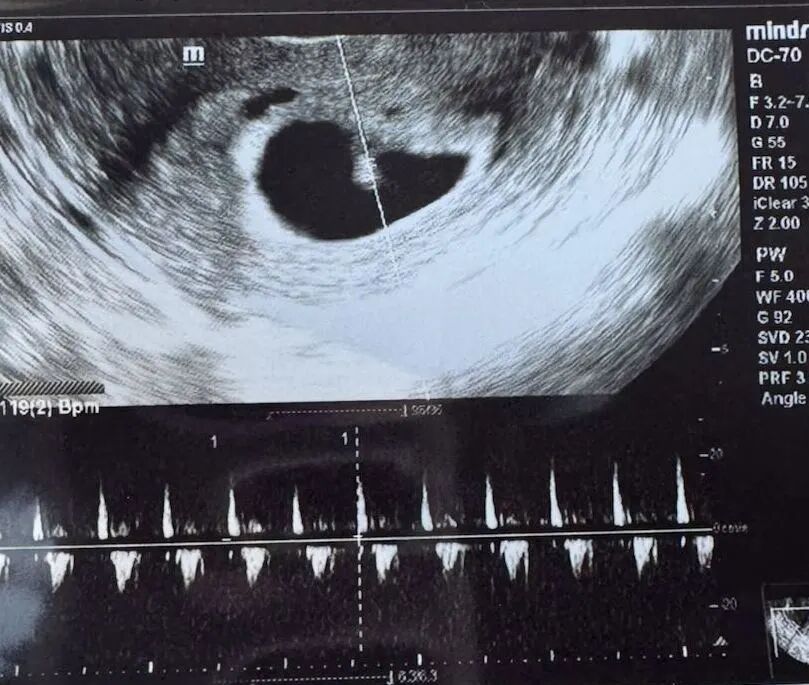

爱妈J的首次B超检查,听一听6周零6天的小宝宝的心跳声!这个小小的生命已经在准妈妈的期待中悄然成长,虽然只有蓝莓大小,但已经有了清晰的心跳强劲而有力!当准妈妈收到宝宝心跳的视频时,感动落泪!期待爱妈顺利从诊所毕业,迎接更加美好的孕期旅程!